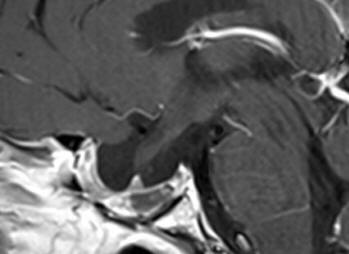

The patient was sent for thorough radio-ophthalmo-endocrine investigations. MRI of the sella with MRA done 16-December-2017 showed the tumor pushing the chiasm and optic nerves with suprasellar extension around 16.2 mm. The tumor has massive infrasellar extension reaching the naso-pharyngeal space abutting it. The tumor dimensions are 37.3x28.6 mm. There is no invasion of the cavernous sinuses. There is fluid level inside the tumor confirming the presence of apoplexy. Visual acuity of the right eye after correction 6/6. The left eye 6/0.05. There is massive scatoma left eye with less in the right eye. Prolactine 470 ng/ml, LH 1.19, testosterone 0.3. Considering the above data trans-sphenoidal approach with MRI control was advised. Mathematically speaking the volume of the tumor with the hypophysis is around 8.8 ml.

Fig:1- Follow up MRI performed 14-January-2019 3 months after completion of radiotherapy.